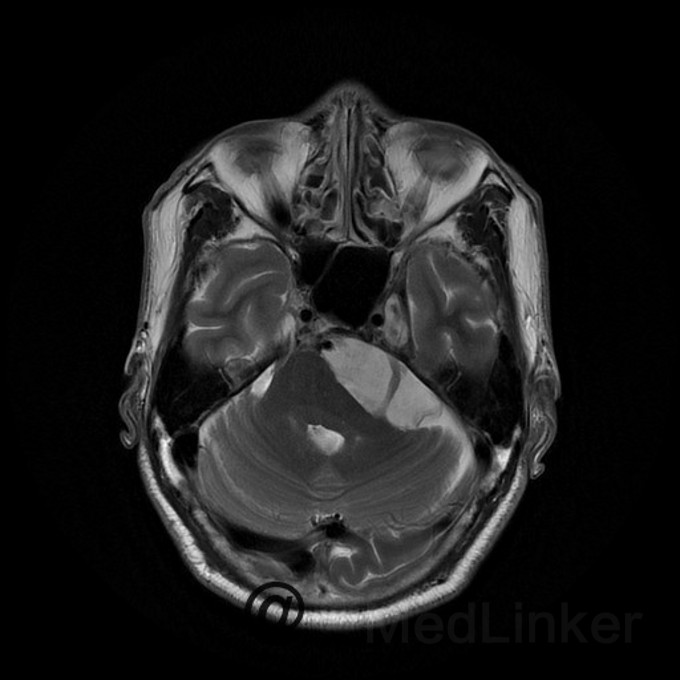

桥小脑区看到一个水样信号影?是蛛网膜囊肿还是表皮样囊肿?

蛛网膜囊肿还是表皮样囊肿都是囊肿,都是T1呈低信号,T2呈高信号,增强都木有强化,两者要怎么鉴别?求赐教

桥小脑区长T1长T2囊状病灶(如图),考虑表皮样囊肿还是蛛网膜囊